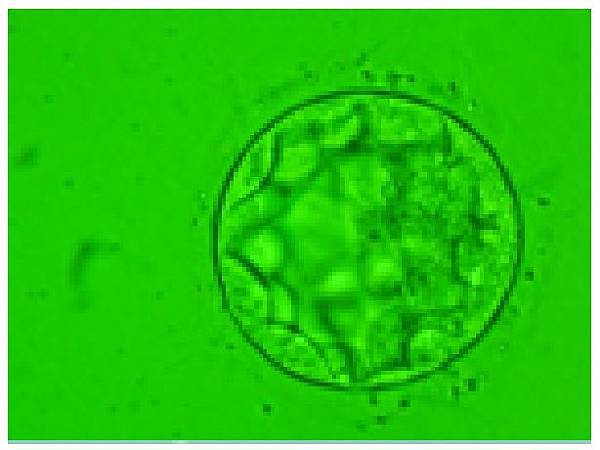

• 生長遲緩(D6、D7)的囊胚

所謂「好的胚胎」是指生長速度及外觀。好的胚胎一般會在取卵後滿五天達到囊胚期(下圖):